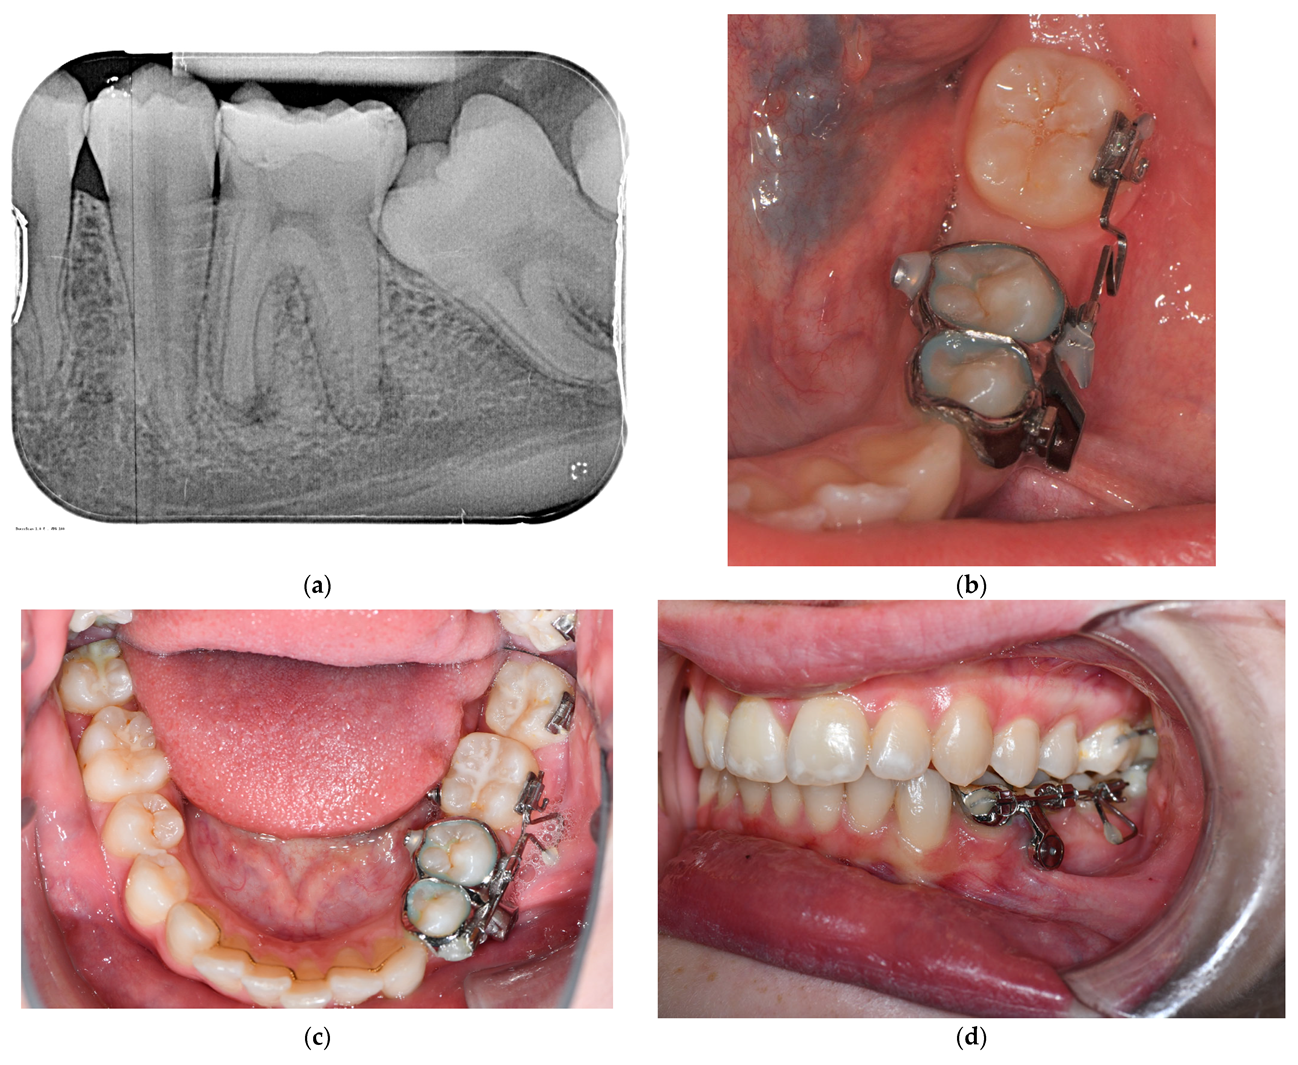

3.3. Treatment Progress